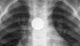

Περισσότερα Διαβάζεται σε 1' ΚΟΙΝΩΝΙΑ Τέλος καλό για το τρίχρονο που κατάπιε ξυραφάκι Αίσια έκβαση είχε η περιπέτεια για το τρίχρονο παιδί που κατάπιε ξυραφάκι και μεταφέρθηκε επειγόντως στο νοσοκομείο, όπου υπεβλήθη εσπευσμένα σε… Newsroom19 Μαρτίου, 2026